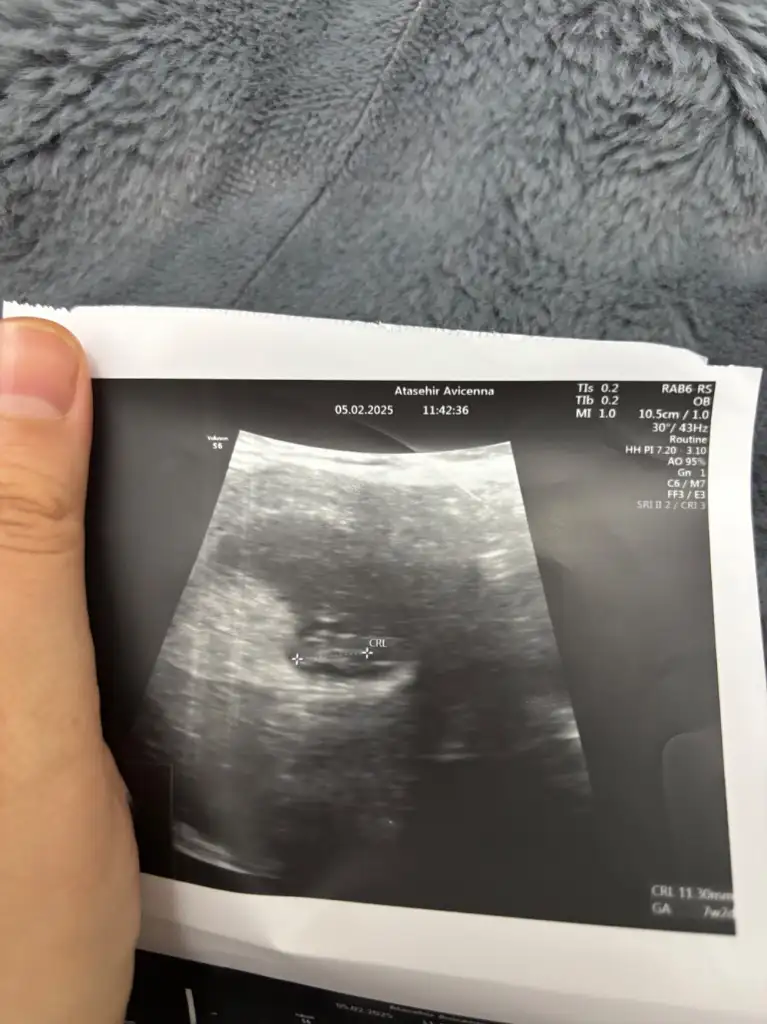

7+4 Du burada şuan 8+4 olduk karından

Erkekk

Ben kıza benzettim